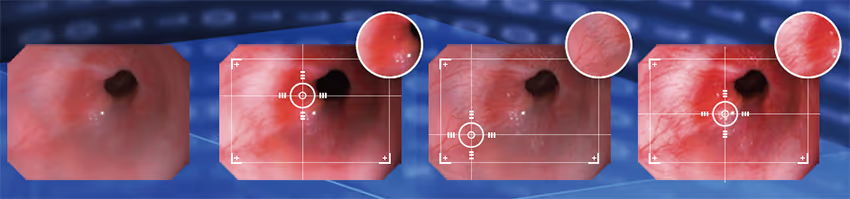

Güçlü algoritmalar, klinik gözlem ve tanıyı kolaylaştırmak için üç modda görüntü ayrıntılarını geliştirir.

Aohua OR-100, rijit endoskop kamera sistemi, çeşitli boyutlardaki tüm rijit skoplarla uyumludur ve köpekler/kediler/egzotik hayvanlar için endoskopik tanı, artroskopik cerrahi, laparoskopik cerrahi vb. gibi hayvan endoskopik tanı ve cerrahisine olanak sağlamaktadır.